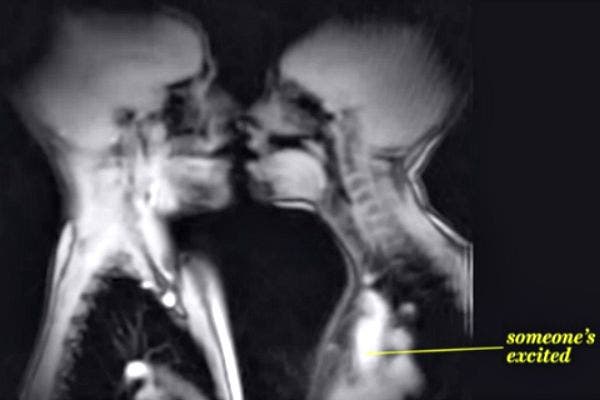

1. Somebody has to make the first move.

MRI, or Magnetic Resonance Imaging, has been around since the 1980s, but recent improvements in resolution and computing have made it possible to makes videos from the scans, and even provide technicians with detailed real-time moving images.

2. Let the French kissing commence.

Ida Sabelis, a Dutch anthropologist and one of the subjects of the study said, "On a certain moment there's sounding through the microphone. The erection is fully visible, including the root."